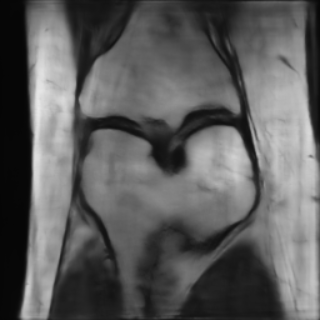

This article presents a novel undersampled magnetic resonance imaging (MRI) technique that leverages the concept of Neural Radiance Field (NeRF). With radial undersampling, the corresponding imaging problem can be reformulated into an image modeling task from sparse-view rendered data; therefore, a high dimensional MR image is obtainable from undersampled $k$-space data by taking advantage of implicit neural representation. A multi-layer perceptron, which is designed to output an image intensity from a spatial coordinate, learns the MR physics-driven rendering relation between given measurement data and desired image. Effective undersampling strategies for high-quality neural representation are investigated. The proposed method serves two benefits: (i) The learning is based fully on single undersampled $k$-space data, not a bunch of measured data and target image sets. It can be used potentially for diagnostic MR imaging, such as fetal MRI, where data acquisition is relatively rare or limited against diversity of clinical images while undersampled reconstruction is highly demanded. (ii) A reconstructed MR image is a scan-specific representation highly adaptive to the given $k$-space measurement. Numerous experiments validate the feasibility and capability of the proposed approach.